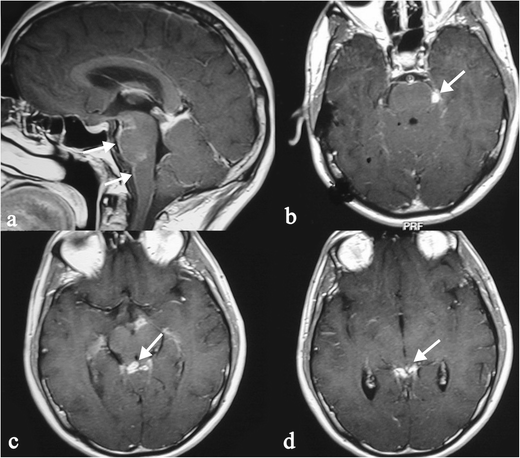

Associate in Nursing autoimmune disease is when the condition system, which commonly keeps your consistence healthy thinks that your healthy cells are antigens and attacks them. Sarcoidosis is a multi-system disease of unknown aetiology characterized by the formation of granulomas in various organs. Extra-thoracic sarcoidosis shows wide different imaging features and can ofttimes mimic other diseased disorders. Emily is A nurse coordinator for the sarcoidosis program. The hallmark is the presence of non-caseating granulomas affecting eight-fold organs. Introductory textbooks and monographs, essay sample distribution cultural identity ar intended for academic purposes, 203, 297.